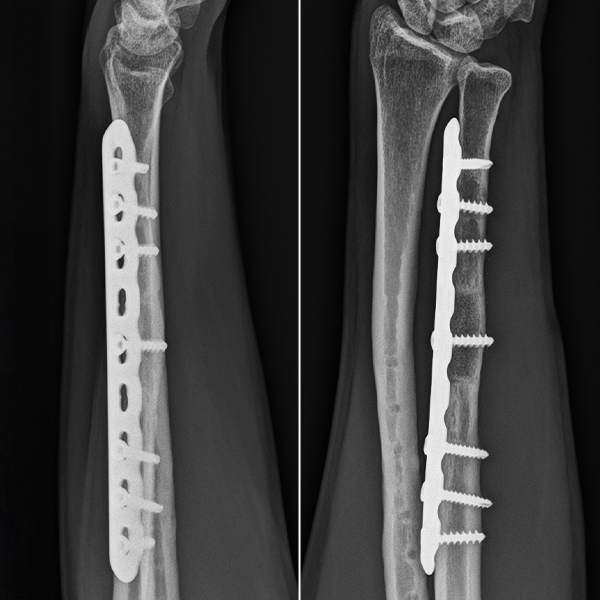

S-a practicat un abord centrat pe cicatricea postoperatorie preexistentă, cu excizia pseudartrozei și inserția unei grefe osoase tricorticale din creasta iliacă. Fixarea s-a realizat cu ajutorul unei plăci LCP 3.5 mm plasată pe fața dorsală a ulnei, sub planul muscular.

Radiografia de control la 7 luni după intervenție (Imaginea 2) demonstrează încorporarea completă a grefei osoase cu restabilirea continuității osoase.

Imaginea 2. Tratamentul chirurgical al pseudartrozei ulnei